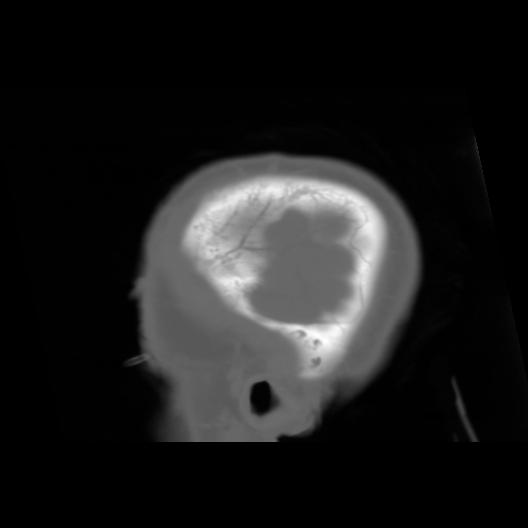

6 CEREBRO,,Sagittal,3.000,CEREBRO,Sagittal,